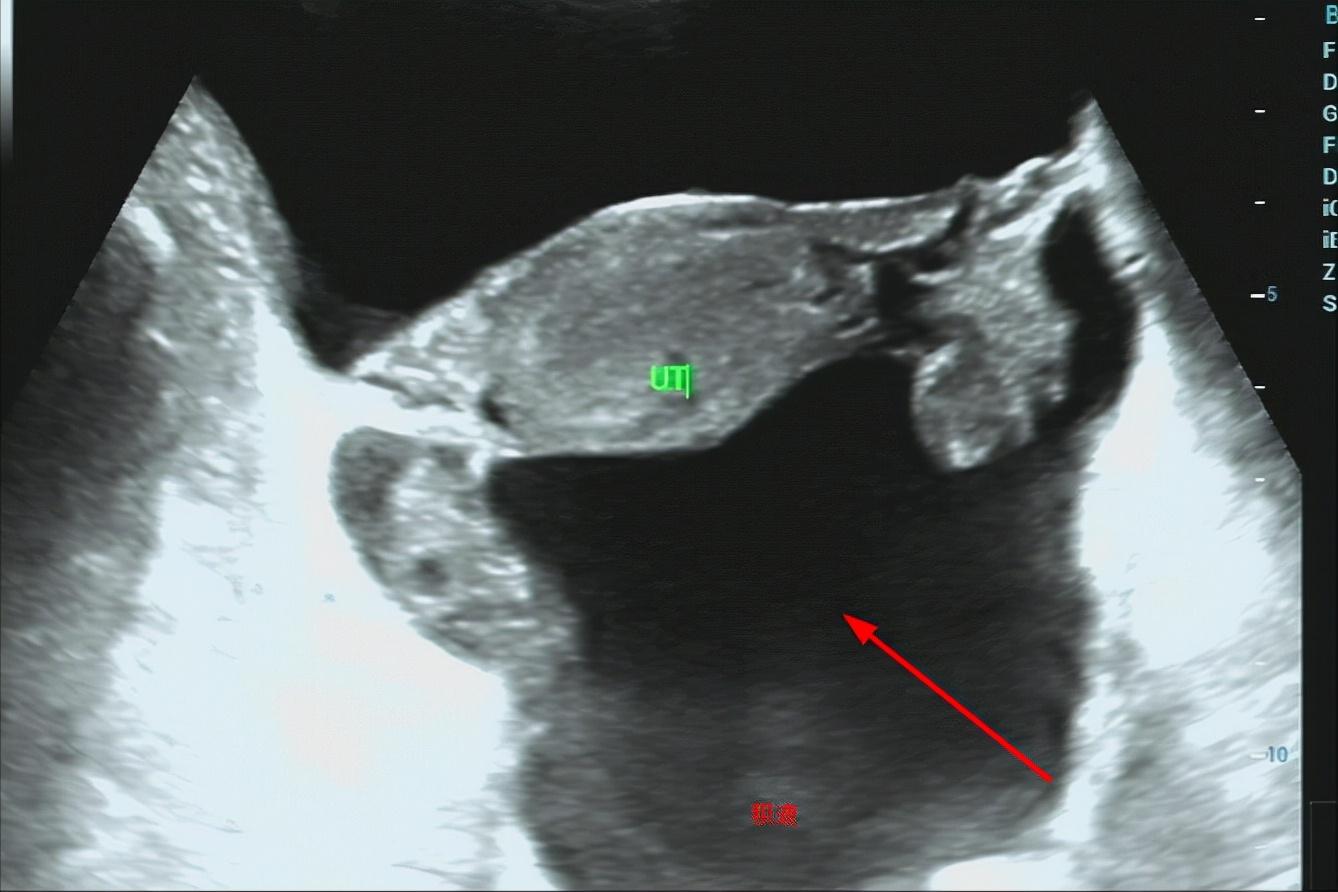

宫外孕破裂,大量积血